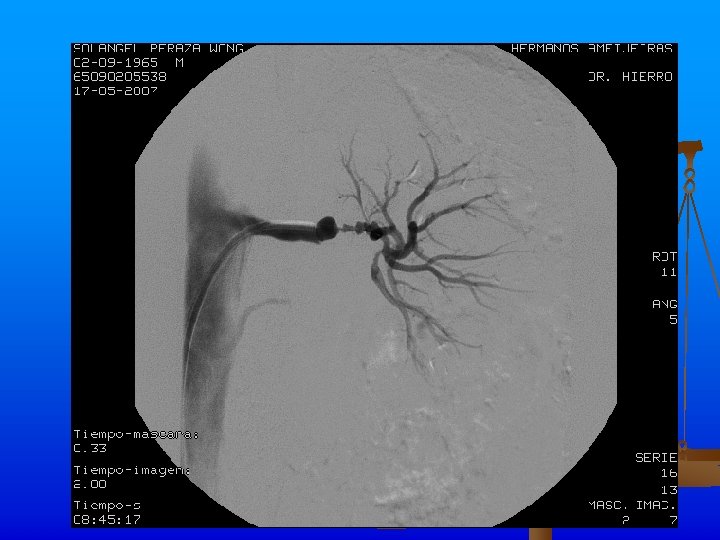

Se realiza angiplastia transluminar percutànea de arteria renal izquierda y se coloca stent de 18 X 4 mm con la administración de 1000 Uds. de heparina y la administración de contraste sin complicaciones